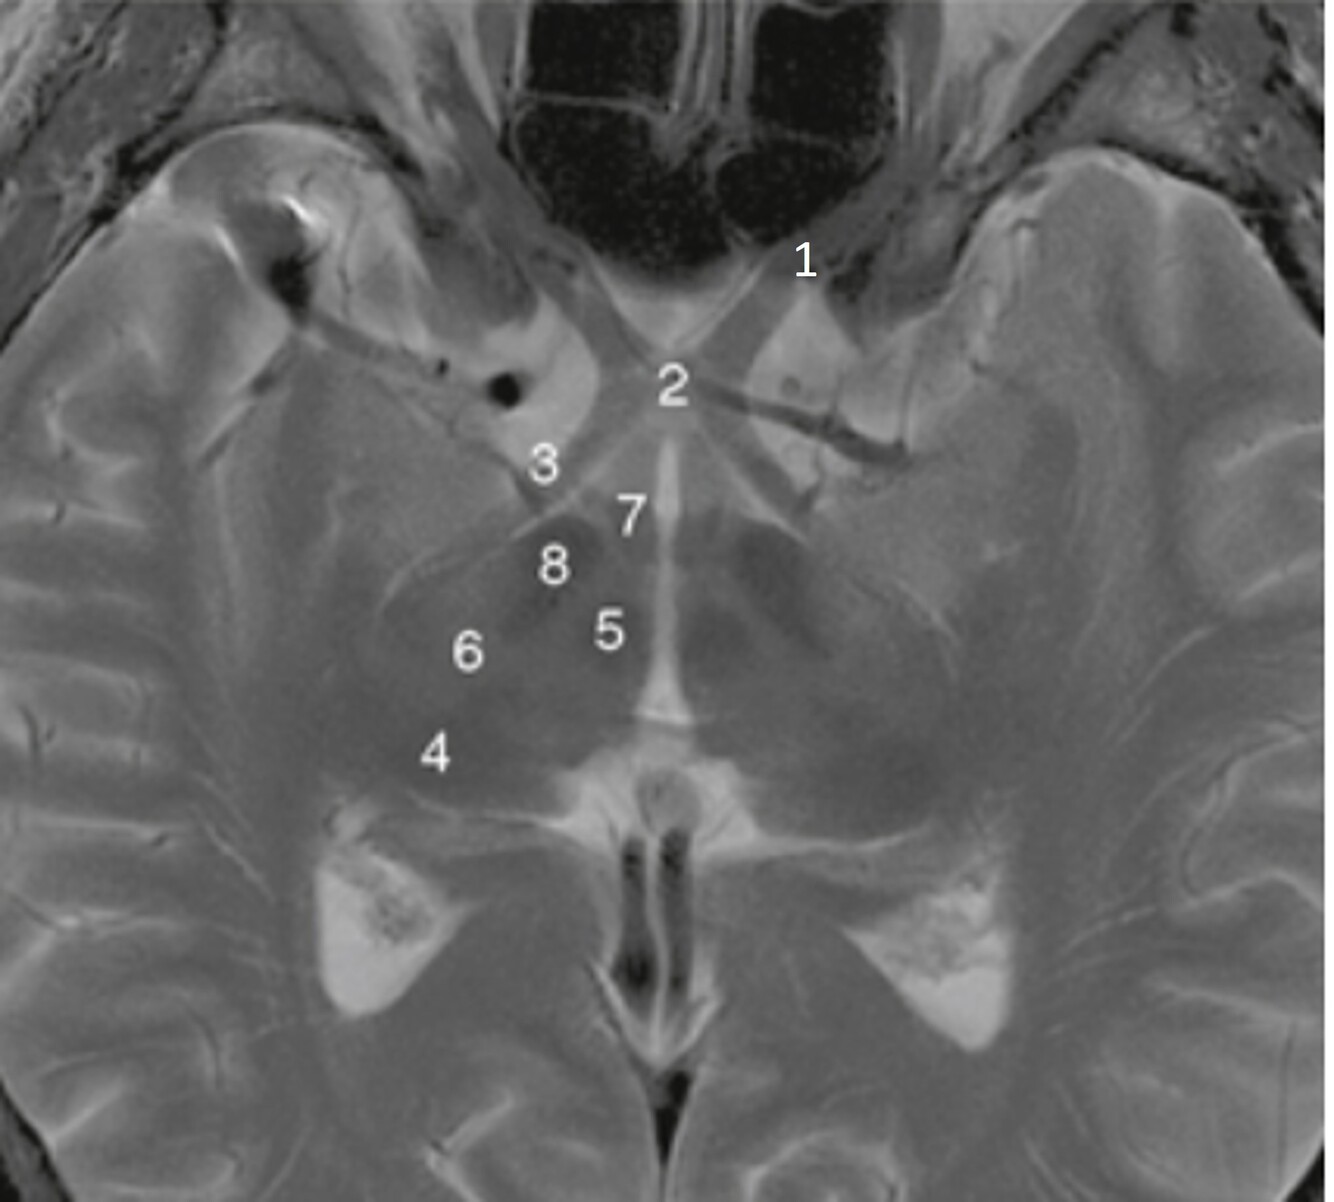

23

Q

Label a,b,c,d,f,g

A

a-Rt lateral fissure

b=Insula

c=Quadrigeminal cistern

d-3rd ventricle

f-Cerebellum

g=Anterior horn (of rt lateral ventricle)

24

Label a-e

a=Septum pellucidum

b=3rd ventricle

c=Lt Thalamus

d=Genu of corpus callosum

e=Splenium of corpus callosum

25

Label f-i

f-Rt lateral ventricle g=Lt foramen of Monro (interventricular foramen) h=Choroid plexus (of rt lateral ventricle) i=Posterior horn (rt lateral ventricle